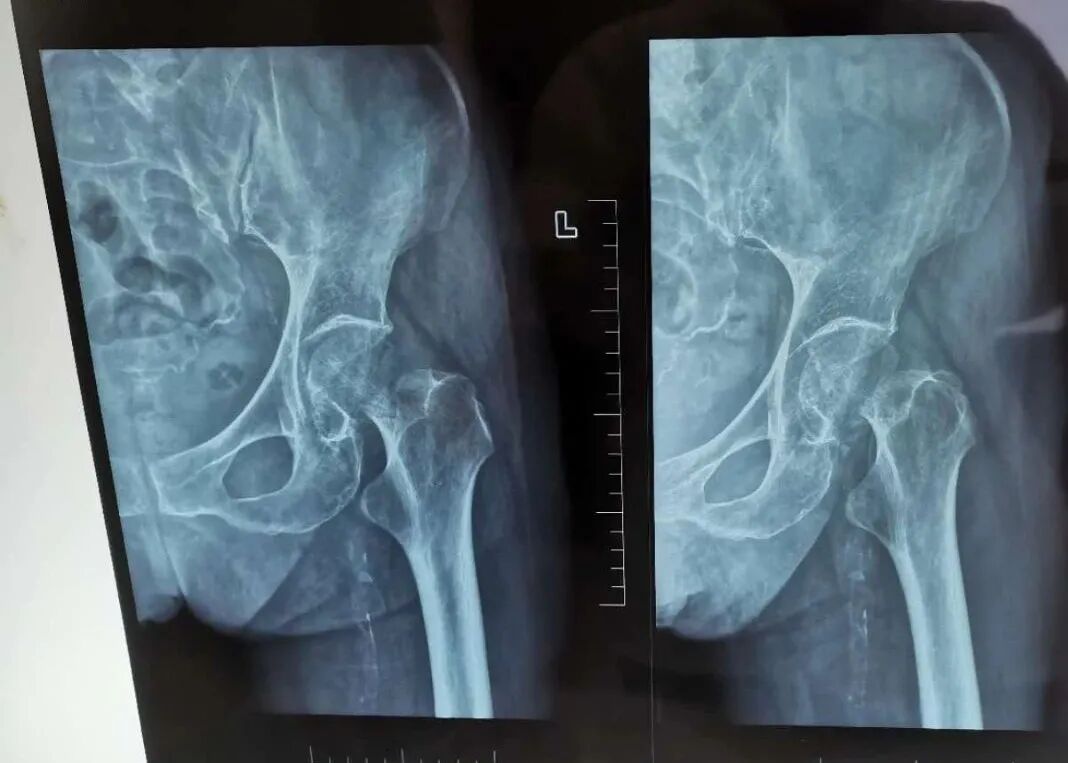

这日,9旬的许阿姨晚上在家附近走路的时候不慎摔倒,当时是左髋部先着地,马上就感觉到疼痛难忍,无法站立、行走,生活不能自理,第二天来到当地的卫生院就诊,被告知左股骨颈骨折,随后转院来到衢州骨伤科医院,门诊以“左股骨颈骨折”收入住院。

许阿姨入院后朱宽宏院长和周亮主任立即查看患者,经询问病史、查体、阅片后诊断为左股骨颈骨折,诊断明确,应该手术治疗。由于许阿姨属于高龄病人,而且还有高血压、痛风、肾衰竭、贫血、冠心病和白内障等病史,所以手术风险极高。朱宽宏院长和周亮主任及多学科团队多次进行详细做病历分析和详尽的术前讨论,最终决定为刘阿姨实施“微创DAA入路人工股骨头置换手术”方案。